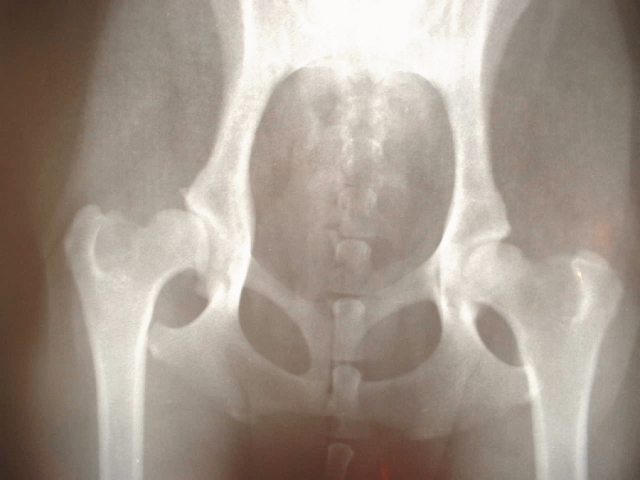

股関節は骨盤側の寛骨臼と大腿骨頭からなる球関節で、広い可動域と強固な安定性を併せ持っています。股関節が音が鳴るとき、痛くないケースでは関節包内の圧力変化や腱の動きが関係していると考えられます。正常な股関節は軟骨や滑液により摩擦が少なく、音が鳴るだけで痛くない場合、関節自体が健康な証拠であることもあります。ただし股関節が音が鳴る頻度が急に増えるときは注意が必要です。